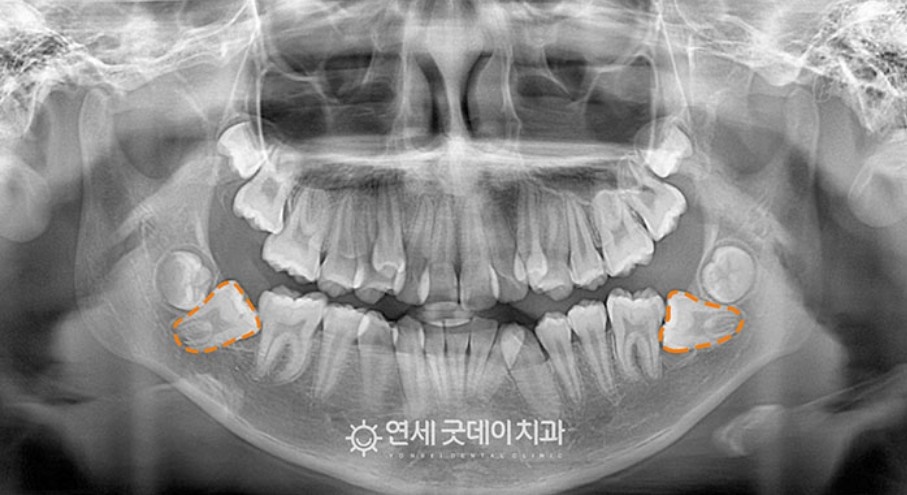

○ 프로필 : 13세 여환

○ 담당과 : 교정과 전문의 + 구강외과 전문의

○ 치료 : 숨어있는 매복치 견인교정

흔히 접하는 매복사랑니와 달리 매복치아는 생소할 수 있습니다.

매복치란 구강 밖으로 나오지 못하고 잇몸이나 뼈 안에 머물러 있는 것을 의미합니다. 이러한 매복치는 염증이나 저작능력 등 여러 문제를 유발할 위험이 있어 주의가 필요한 치아입니다.

저희 병원에 찾아주신 환자분(13세 여환자)은 하악의 양측 어금니 모두 매복된 케이스라 구강외과 전문의 협진 치료로 들어갔습니다.

환자 스스로도 이러한 문제로 방문해 주셨으며, 엑스레이 촬영 후 하악 양쪽 제2 대구치가 매복되어 있는 것을 발견할 수 있었습니다.

엑스레이 사진을 보면 매복치아 형태를 볼 수 있습니다. 본래, 정상적으로 맹출되어야 하지만 온전히 누워 있고, 환자분도 별 다른 통증을 느끼지 못해 뒤늦게 인지하게 됐습니다.